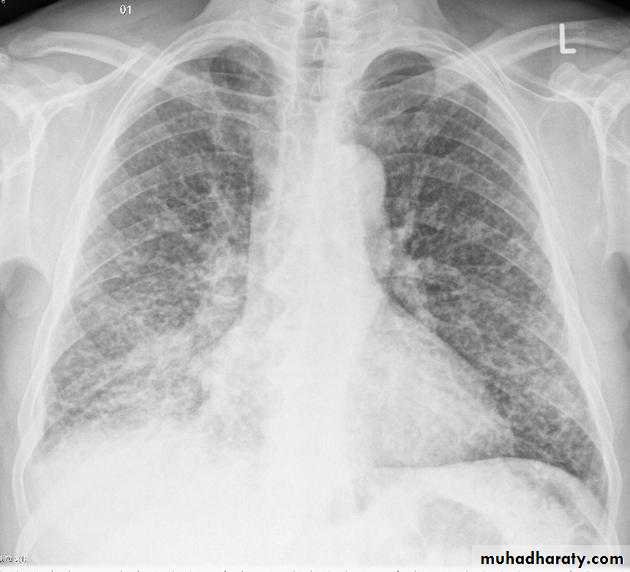

Loculated effusion

Occurs secondary to adhesions which form between visceral and parietal pleuraAdhesions more common with blood(hemothorax) and pus (empyema)

Loculated effusions have unusual shapes or positions in thorax

hydropneumothorax

If both a pneumothorax and a pleural effusion occur together, it is called a hydropneumothoraxA hydropneumothorax is usually due to trauma, surgery, bronchopleural fistula

It is characterized by an air-fluid level in the hemithorax

A straight edge,indicative of a fluid interface, in this case an air-fluid interface, is seen on the right.